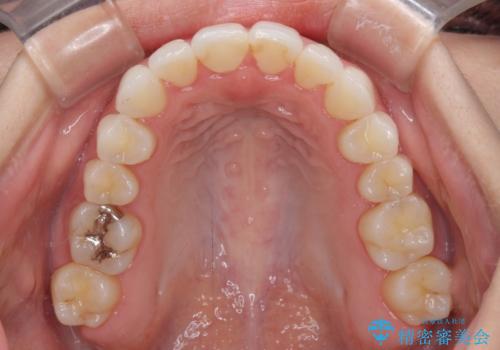

前歯のクロスバイトを治したい インビザラインによる矯正治療

- 前歯のデコボコとクロスバイトを治したいとのことで来院された患者様です。

上下顎ともに歯列全体の側方拡大とIPR(歯と歯の間を削る)によってデコボコとクロスバイトが解消するように設計し、インビザラインにより治療を行うこととしました。

下顎骨の左側への骨格的なずれが強く、上下の正中の位置合わせや奥歯の咬み合わせ構築に苦労しました。